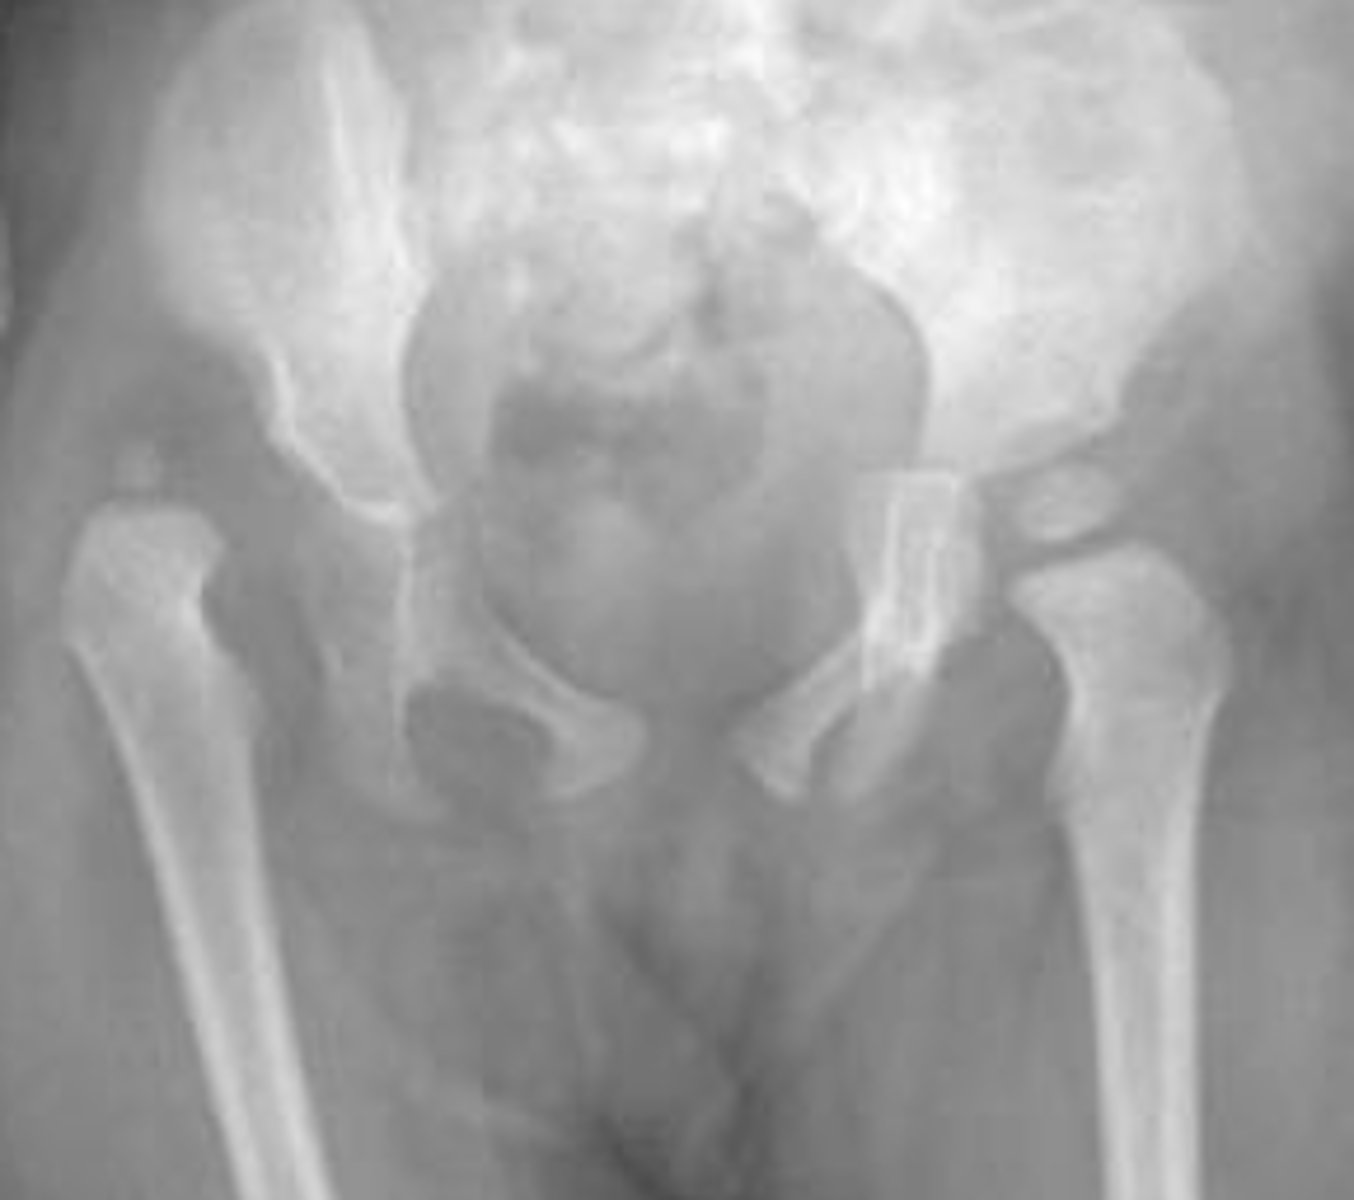

Based on the two age ranges what do each of these individuals have respectively?

Answer

13-16 y/o: SCFE

5-8 y/o: Leggs Cathe Perthes

Leggs Cathe Perthes

Congenital AVN of the hip commonly in children around 4-8 y/o

What does this person have?

Developmental dysplasia of the hip